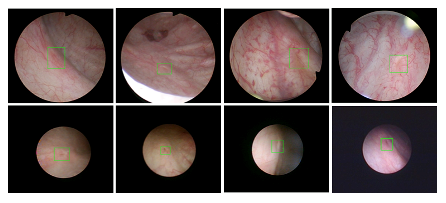

伟德国际1949始于英国医疗机器人研究院—深睿医疗人工智能医学视频联合实验室成立于2018年7月。PI包括来自于交大生医工公司和电院的三位教授,平台建设目标是将人工智能实时地用到临床医学中去,研究方向包括:1. 建立内窥镜人工智能辅助诊断系统,通过对病灶和解剖结构的实时识别来辅助医生更好地进行微创诊断和治疗;2. 以个性化、定量化的精准诊疗技术为研发目标,重点开展医学影像智能诊断、医学可视化及计算机辅助手术规划、AI及大数据分析在临床诊疗流程中的集成应用等方向的研发。试图利用AI技术、大数据分析技术、3D打印技术、虚拟现实及增强现实技术促进临床的影像诊断、治疗方案设计、预后预测分析等诊疗环节的智能化提升与技术变革;3. 面向运动医学康复、神经退行性疾病量化诊断,以及其他与人体运动相关的疾病诊疗、康复应用,开展视觉三维人体运动的测量、分析与识别研究,通过基于深度学习的视觉检测识别以及相关大数据分析,为相关疾病的诊疗和康复提供AI辅助。具体临床应用包括:关节镜手术术后康复指导和评估、帕金森病的量化诊断、精神疾病的量化诊断与评估、儿童异常行为分析等。

近年来,联合实验室发展了泌尿镜手术实时识别技术,人体姿态精确识别技术,另外围绕小儿先心病手术、肝癌消融手术、数字口腔诊疗的智能化提升等内容进行应用研发。